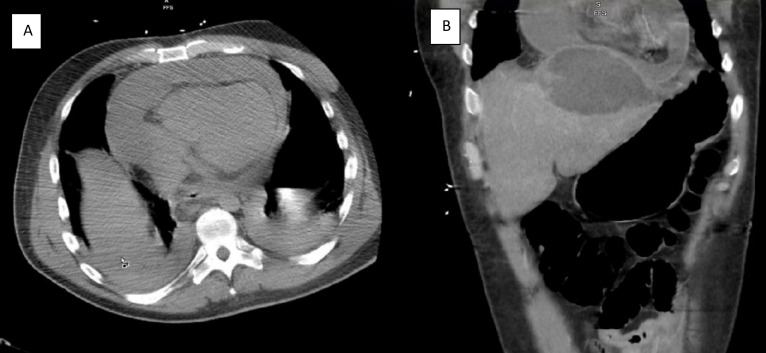

Bedside echocardiogram revealed a large pericardial effusion (video 1), but initial subxiphoid pericardiocentesis was unsuccessful due to purulent fluid return prior to accessing the pericardium. A CT scan of the chest, abdomen and pelvis (figure 1) revealed a large left hepatic lobe abscess and further described the pericardial effusion as larger anteriorly than posteriorly. He was empirically started on piperacillin/tazobactam and metronidazole and required haemodynamic support as well as continuous renal replacement therapy after developing hyperkalemia due to acute renal failure.

Figure 1.

(A) CT scan of the abdomen: coronal view demonstrating hepatic and pericardial abscesses. (B) CT scan of the chest: transverse view demonstrating circumferential pericardial abscess.